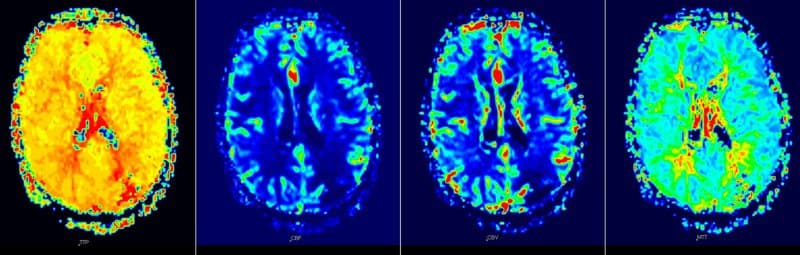

Về mặt kỹ thuật có hai phương pháp chính để đo lường tưới máu não trên MRI: kỹ thuật có sử dụng thuốc tương phản từ và kỹ thuật không sử dụng thuốc tương phản từ. Kỹ thuật có sử dụng thuốc tương phản từ được áp dụng thông dụng hiện nay là Dynamic susceptibility contrast-enhanced MRI perfusion (DSC MRI perfusion) với bơm thuốc tương phản từ gốc Gadolinium vào lòng mạch và sử dụng chuỗi xung T2* trên MRI thông qua các thuật toán và sự hỗ trợ của hệ thống máy tính để tính ra các thông số tưới máu não như CBF, CBV, MTT, Tmax và hiển thị bằng mã hóa màu tưới máu nhu mô não.

Kỹ thuật không tiêm thuốc tương phản từ là arterial spin labeling (ASL MRI perfusion) chỉ cung cấp thông tin về chỉ số CBF và mã hóa màu tưới máu nhu mô não.

Cả hai phương pháp này có ưu/nhược điểm riêng và đang được áp dụng tại Vinmec. Hình ảnh tưới máu não không tiêm thuốc tương phản từ đơn giản, dễ thực hiện, có thể lập đi lập lại nhiều lần và cung cấp thông tin ban đầu cho các bác sỹ quyết định chẩn đoán. Trong trường hợp có bệnh lý các bác sỹ sẽ chỉ định kỹ thuật tưới máu não có tiêm thuốc tương phản để khẳng định chẩn đoán.